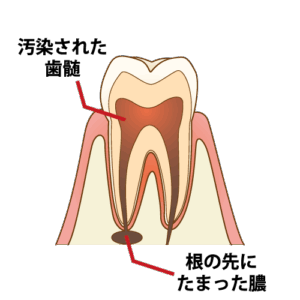

⏫①茶色くなっている部分が、虫歯で感染した神経の部屋です。この部分を数回に分けて綺麗に治療していきます。

⏫②歯の中の治療をしていくので、治療の入り口を作らなければいけません。

神経の感染部分まで機械を使って削っていきます。

※ここから5〜7日に1回のペースで通っていただきます。